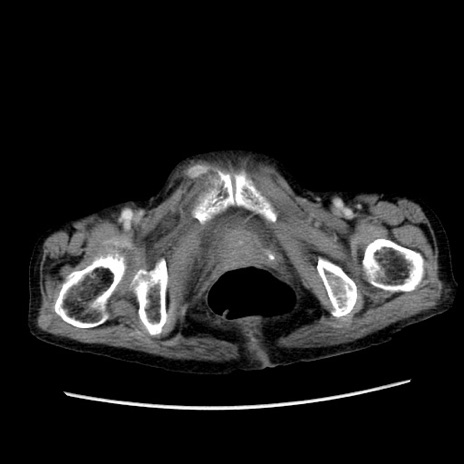

症例25(横断像)

【症例】80歳代女性

【主訴】胸のつかえ感

【現病歴】約9時間前に食後から胸のつかえた感じあり、嘔吐あり、来院。

【既往歴】胃癌(全摘)、胆摘、虫垂炎

【身体所見】心窩部に圧痛あり、反跳痛なし。

【データ】WBC 5700、CRP 0.05